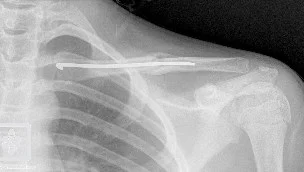

- Surgical Treatment

- ORIF by Plate and Screws (standard)

- Elastic nail ?